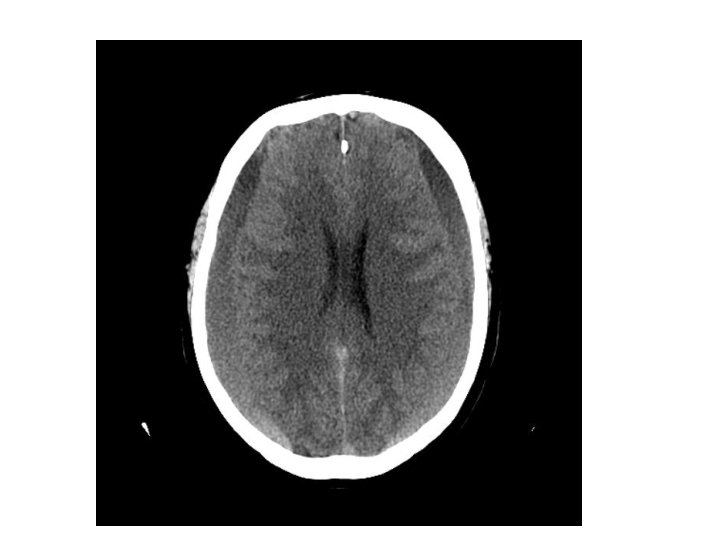

Chronic Subdural haematoma • • Hypodense lesion There might not be midline shift If asymptomatic, serial CT monitoring If symptomatic, burr hole craniostomy